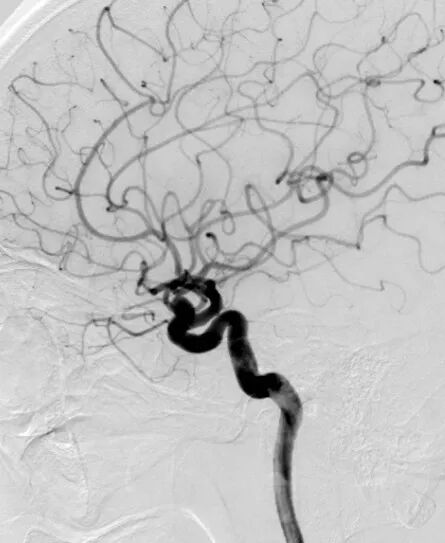

术前影像学检查CTA显示右侧颈内动脉海绵窦段巨大型动脉瘤。

术前3D显示右侧颈内动脉海绵窦段巨大型动脉瘤

DSA正位造影

DSA侧位造影